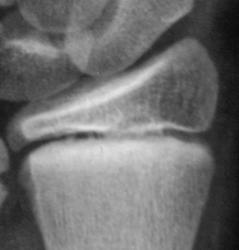

Травма. Пациент направлен хирургом в рентгеновский кабинет для рентгенологического исследования лучезапястного сустава.

Как будем характеризовать линию перелома коллеги?

Вот она - натуральная  "зеленая ветка"!!!

показательный снимок этого перелома

Дело в том, что в данном случае не одна а несколько линий перелома.

Кроме основного – "зеленая ветка" – другой недостоверен: может быть артефактом. На боковой рентгенограмме полоса слишком чёткая для нерезкого в целом снимка, похожа на полосы в области запястных костей. Там нет переломов? Подмигивает В прямой проекции обе линии принадлежат поднадкостничному перелому.